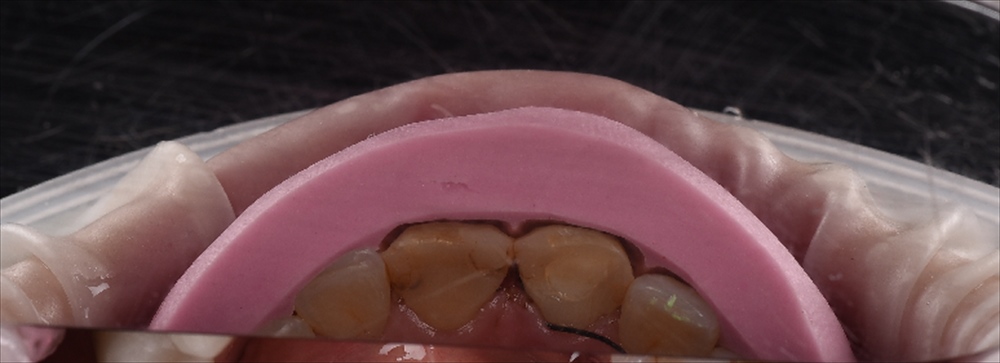

ここから歯をなるべく削らない作戦を技工士の間中とたてガイドを作成

見て頂くと分かると思いますが、前歯2本のみ0.7削り他はノンプレップ(削らない)です。